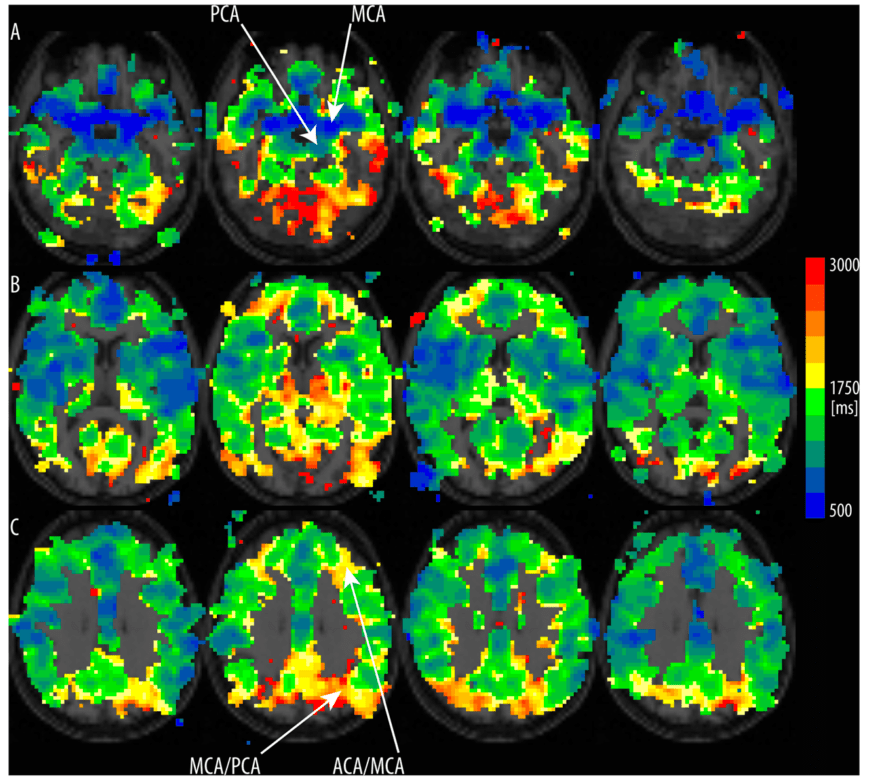

In inversion-recovery sequences such as for VASO, T1-relaxation processes can affect the image contrast while a volume is being acquired. In the 2D-SMS sequence, the individual slice-groups are acquired consecutively. This means that adjacent slices can have different T1-weightings. For short TIs ( < tissue T1), this can result in different signal intensity across the brain volume imaged (see figure above). This is different for 3D-EPI. The fact that in 3D-EPI, the entire brain volume has the same effective TI can be advantageous with respect to these TI-inconsistencies across slices. The different effective T1-weighting and the correspondingly different signal across k-space segments in 3D-EPI, however, can result in inhomogeneous signal distribution across k-space. This can result in image blurring along the second phase encoding direction. To account for this and preserve the available MR signal across k-space segments, our 3D-EPI-VASO sequence uses variable flip angle modulations. The concept of using variable flip angles to account for T1-decay during a multi-shot 3D-readout is adapted from Gai et al. 2011.

The figure below shows three potential flip angle distributions, their corresponding PSF and example images.

- The first column refers to the application of the Ernst angle, which is in the range to 18 deg for typical VASO values. This means, however, that at the end of the readout there is a lot of z-magnetization left that could have been harvested to increase the SNR.

- The second column refers to a distribution, where the flip angle increases between segments with a faster rate then what the T1-relaxation can account for. This results in more magnetization been harvested and larger SNRs. However, it also means that the k-space segments have inconsistent weighting, which results in a broader PSF and signal blurring.

- In the third column, an additional cut-off is introduced. The results means that even more z-magnetization is harvested compared to the middle column. Thus it have an even higher SNR than the middle column. With such an asymmetric k-space weighting, however, the PSF becomes complex and has an imaginary part that can result in destructive interference between neighboring k-space segments (see negative side-lobes of the PSF). These side-lobes can partly account for the blurring in the middle column, while maintaining the high SNR.

Based on these considerations it can be beneficial to introduce a bit of RF-clipping

Since the variable flip angle is adjusted for one T1 compartment only, other T1 compartments (E.g. WM and GW) will have a different point spread function.

Often, this can result in a edge enhancement artifact. as shown below.